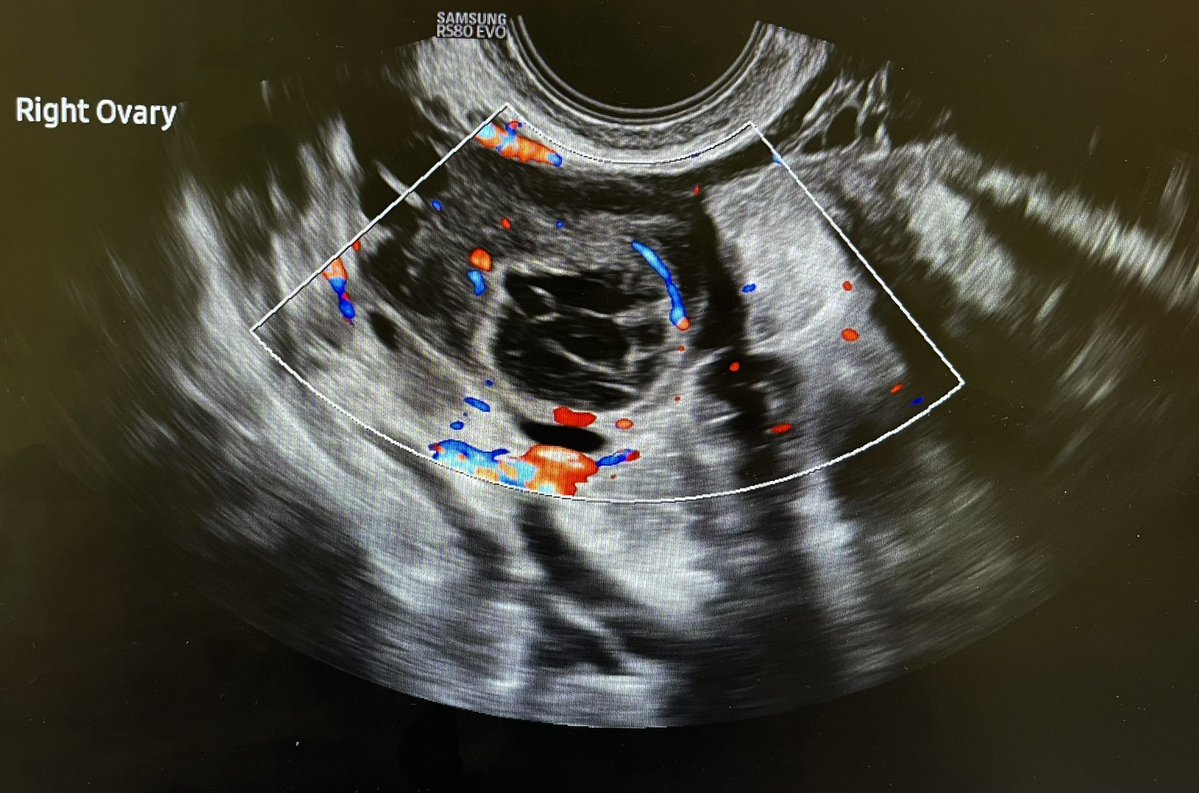

@DeeloOfficial

Deelo

2 days

54F with right flank pain and haematuria. Solid heterogeneous right renal mass with vascularity. ? Renal cell carcinoma. @Rad_Munagi @AjuboDaso